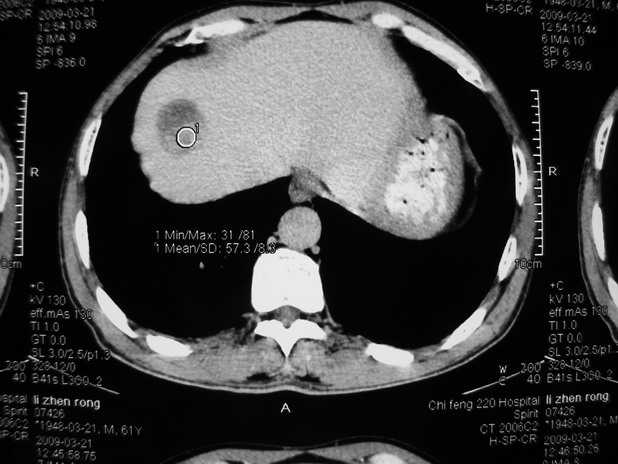

以下是引用余辉在2009-3-21 21:36:00的发言:[br]图像太乱了,建议楼主直接将强化数据按顺序列出来,病灶位置较表浅薄,有肝炎病史,灶内实性成分有显著强化,动脉期约60hu,考虑肝癌可能性大,进一步检查。